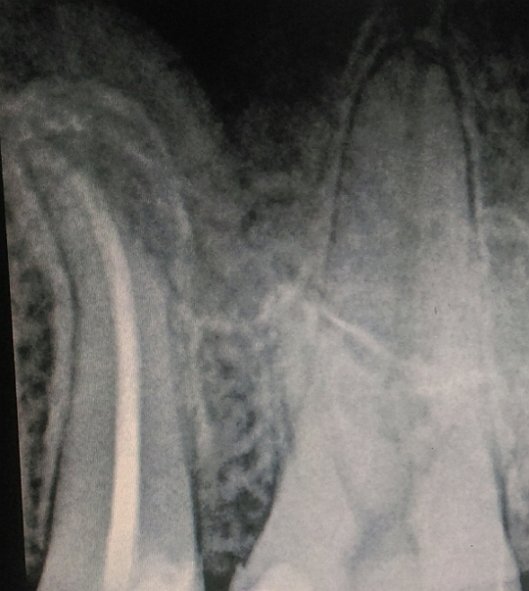

В подростковом возрасте мне сделали резекцию передних зубов из-за кисты. Но спустя примерно 15 лет над зубом образовался, на ощупь, шарик и очень неприятное напряжение под зубом. Я пошла к врачу, он отправил на снимок, но так и не смог мне помочь, и отправил к другому стоматологу, но попасть к нему я так и не смогла.

У вас так называемый рецидив. Обратитесь к хирургу, думаю, данный зуб придется удалить.